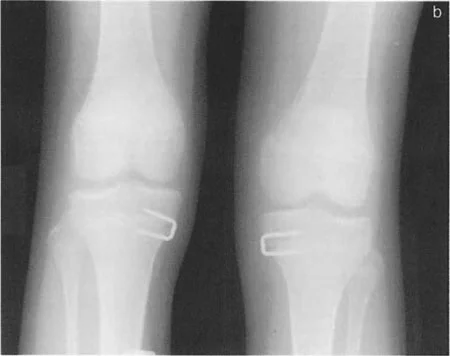

تثبيت الصفيحة المشاشية المؤقت بالدبابيس (Hemi-epiphysiodesis)

تعتبر عملية تثبيت الصفيحة المشاشية المؤقت بالدبابيس (Hemi-epiphysiodesis) خيارًا علاجيًا فعالًا لتصحيح التشوهات الزاوية أو تفاوت طول الأطراف في الأطفال الذين لا يزالون في طور النمو. هذه العملية أقل تدخلاً من عمليات قطع العظم وتثبيته.

- المبدأ: يتم وضع دبابيس معدنية على جانب واحد من صفيحة النمو (في حالة التشوهات الزاوية) أو على صفيحة النمو بأكملها في الطرف الأطول (لتصحيح تفاوت الطول). تعمل هذه الدبابيس كـ "مرساة" أو "نقطة تثبيت" تبطئ النمو في تلك المنطقة، بينما يستمر النمو الطبيعي في الجانب الآخر من الصفيحة أو في الطرف الأقصر.

- يمكن إزالة الدبابيس للسماح باستئناف النمو، مما يجعل التصحيح مؤقتًا وقابلًا للتعديل.

- مؤشرات الاستخدام:

- تصحيح الانحرافات الزاوية حول الركبة أو الكاحل (مثل الركبة الروحاء أو الفحجاء).

- تقليل تفاوت طول الأطراف في الطرف الأطول.

- تُجرى للمرضى الذين لديهم نمو متبقٍ كافٍ لتحقيق التصحيح المطلوب.